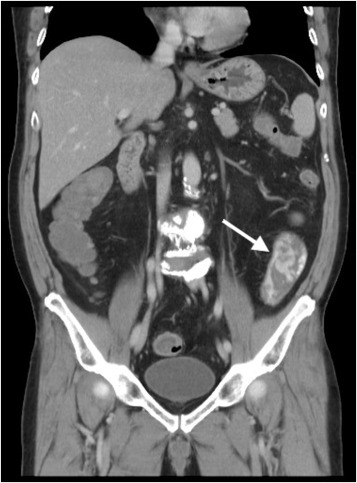

A 65-year-old man was referred to our emergency department for surgical intervention of refractory post-polypectomy hemorrhage. The patient had a medical history of hypertension, diabetes, and gout. He was not taking aspirin or other anticoagulant medication. According to the referral sheet, the polyp was 2 cm in diameter with a thick stalk in the descending colon. The referring physician had administered a prophylactic injection of diluted epinephrine into the polyp base, with two prophylactic endoclips placed before the procedure. Massive bleeding developed immediately after the procedure, and the referring physician attempted hemostasis with further injection therapy and heat-probe coagulation; however, it was not successful. The patient went into shock and was transferred to our hospital 2 h after the procedure. At the emergency department, the patient was pale and hypotensive, with a systolic blood pressure of 84 mmHg with tachycardia (heart rate: 110 beats/min). Blood test revealed a drop in hemoglobin from 14.2 g/dL to 8.9 g/dL and a normal coagulation profile. An emergent abdominal computed tomography (CT) scan revealed active contrast extravasation in the descending colon (Figure 1 , arrow), and a proctology surgeon was consulted for surgical intervention. After discussion with the patient, the patient requested a second attempt at colonoscopy to control his bleeding, and an emergent colonoscopy was performed. A large amount of fresh bloody content was found between the rectum and the descending colon. After copious irrigation with water and positional change, the bleeder source was identified (Figure 2 ).

Abdominal computed tomography span revealed active contrast extravasation from ...

Figure 1.

Abdominal computed tomography span revealed active contrast extravasation from the descending colon (arrow).